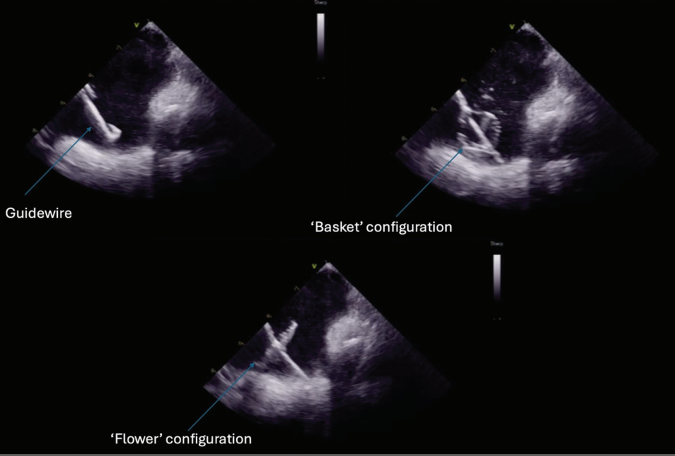

diagnosed 1.5 years prior. He was previously cardioverted and maintained on dronedarone with recurrence of symptomatic persistent AF, prompting referral for catheter ablation. He subsequently underwent AF ablation utilizing a pentaspline catheter. Ultrasound guidance was utilized to obtain 3 points of vascular access in the right femoral vein (Figure 1). ICE guidance was utilized for transseptal access and to guide catheter manipulation while ensuring optimal contact with ablation (Figures 2 and 3). Meticulous sheath management was employed, ensuring performance of all sheath exchanges while aspirating to reduce likelihood of air bubble introduction. A baseline electroanatomic voltage map was obtained for a substrate-based approach, which showed a predominantly healthy left atrium despite persistent AF though notably early in its course (Figure 4). There was spontaneous induction of AFL with a cycle length of ~280 ms and response to entrainment and activation mapping most consistent with typical AFL. The decision was made to proceed with PV isolation with confirmation of antral level isolation without significant encroachment on the posterior wall on a post-ablation voltage map (Figure 5). The cavotricuspid isthmus line was outlined on the EAM system with ICE while ensuring the intended ablation path was not in direct proximity to the right coronary artery. Ablation was then performed utilizing the pentaspline catheter in flower configuration after pre-administration of nitroglycerin and phenylephrine with termination of AFL and demonstration of bidirectional block post ablation. Total fluoroscopy time was ~4 minutes, the majority of which was utilized for the typical flutter ablation. The patient tolerated the procedure well and was discharged home 6 hours later. He continues to do well in outpatient follow-up.

Highlighted in this case are key tenets in our procedural approach to PFA. First, similar to other ablation technologies, the majority of complications are usually vascular in origin. These complications are largely mitigated with appropriate ultrasound guidance technique to vascular access, as was demonstrated in the MANIFEST-17k registry.16 The need for meticulous sheath management to reduce air bubble introduction cannot be overstated given the large sheath profiles utilized, to reduce the risk of stroke and coronary air embolism. We maintain that ICE guidance and EAM play a pivotal role in guiding ablation. This is important to ensure adequate contact for optimal energy delivery as there is increasing data highlighting its importance for durability.17

Additionally, the ease of ablation with these large footprint PFA catheters also raises concern of collateral damage to neighboring healthy myocardium such as the posterior wall when perhaps only PVI is the intent. This effect in some instances can be proarrhythmic. The ability provided by these tools comes with significant responsibility to be judicious with ablation lesions which can certainly be better optimized with EAM and ICE guidance. The clinical impact of this will likely be better delineated as we have large-scale, long-term follow-up data. Additionally, ICE and EAM guidance also facilitate a low or no fluoroscopy workflow as there is more data being published on the feasibility of this approach.18 This builds upon the significant trend towards zero-fluoroscopy procedures with thermal ablation platforms, which impact both the patients and EP team.